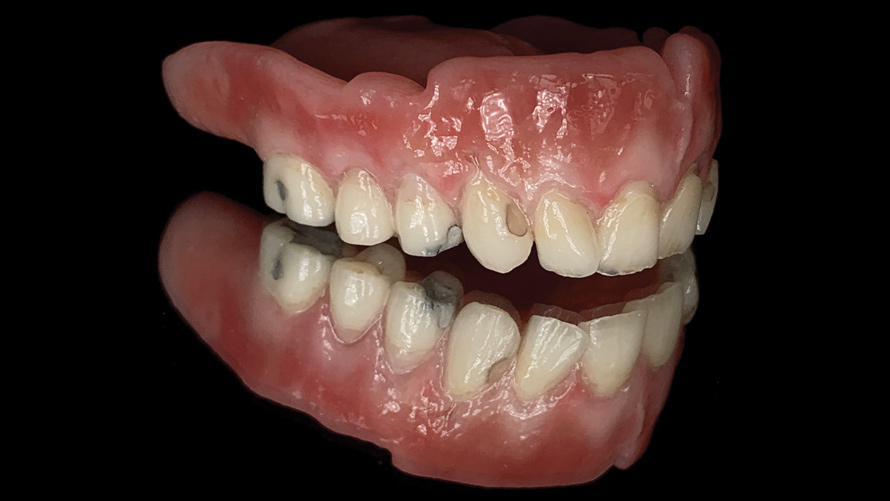

(16.) Photograph of failing implant prosthetics that may require specialty care taken with a smartphone and an EALS device.

Figure 16

(17.) Photograph of failing implant prosthetics that may require specialty care taken with a smartphone and an EALS device.

Figure 17